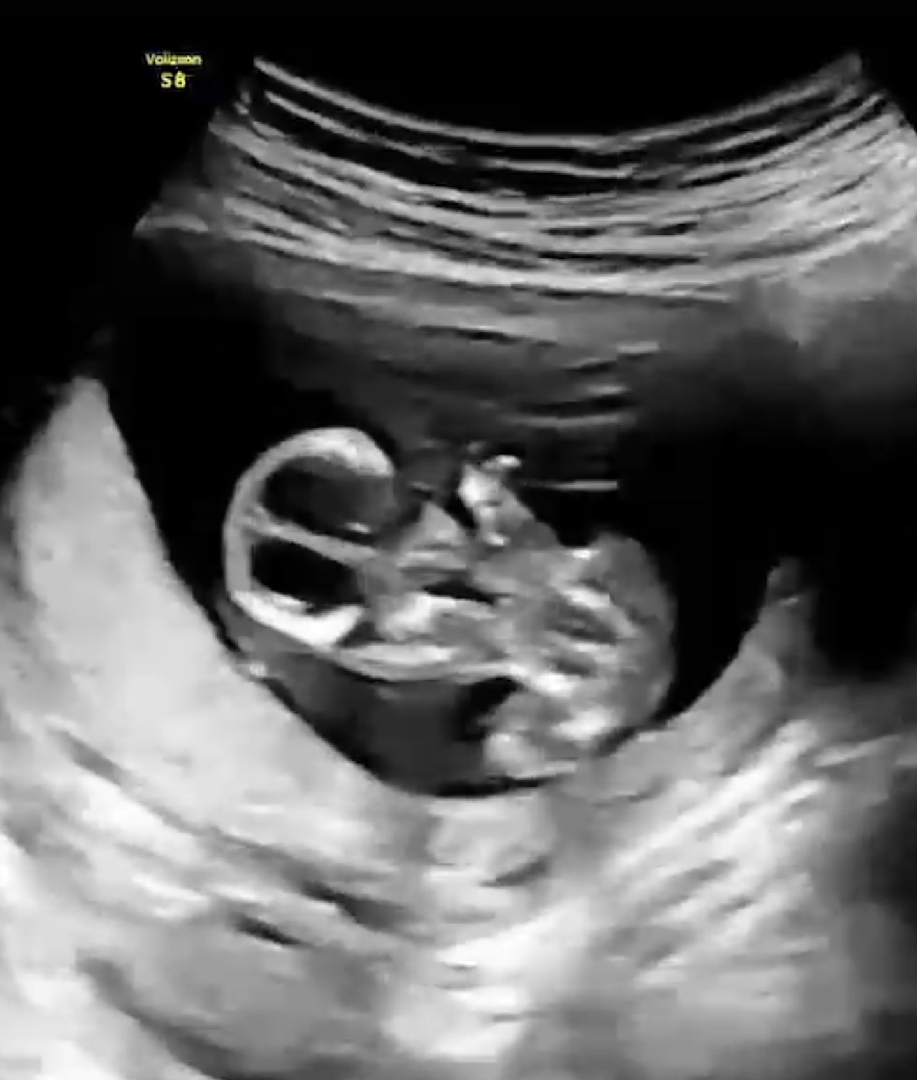

다리사이가 아니라 머리부분과 가슴부분??! 이 나왔네요 😅

성별 이렇게도 보이는분 계신가요?

밑에서 배둘레 재주신다고 하다가 다리사이 보인거에요